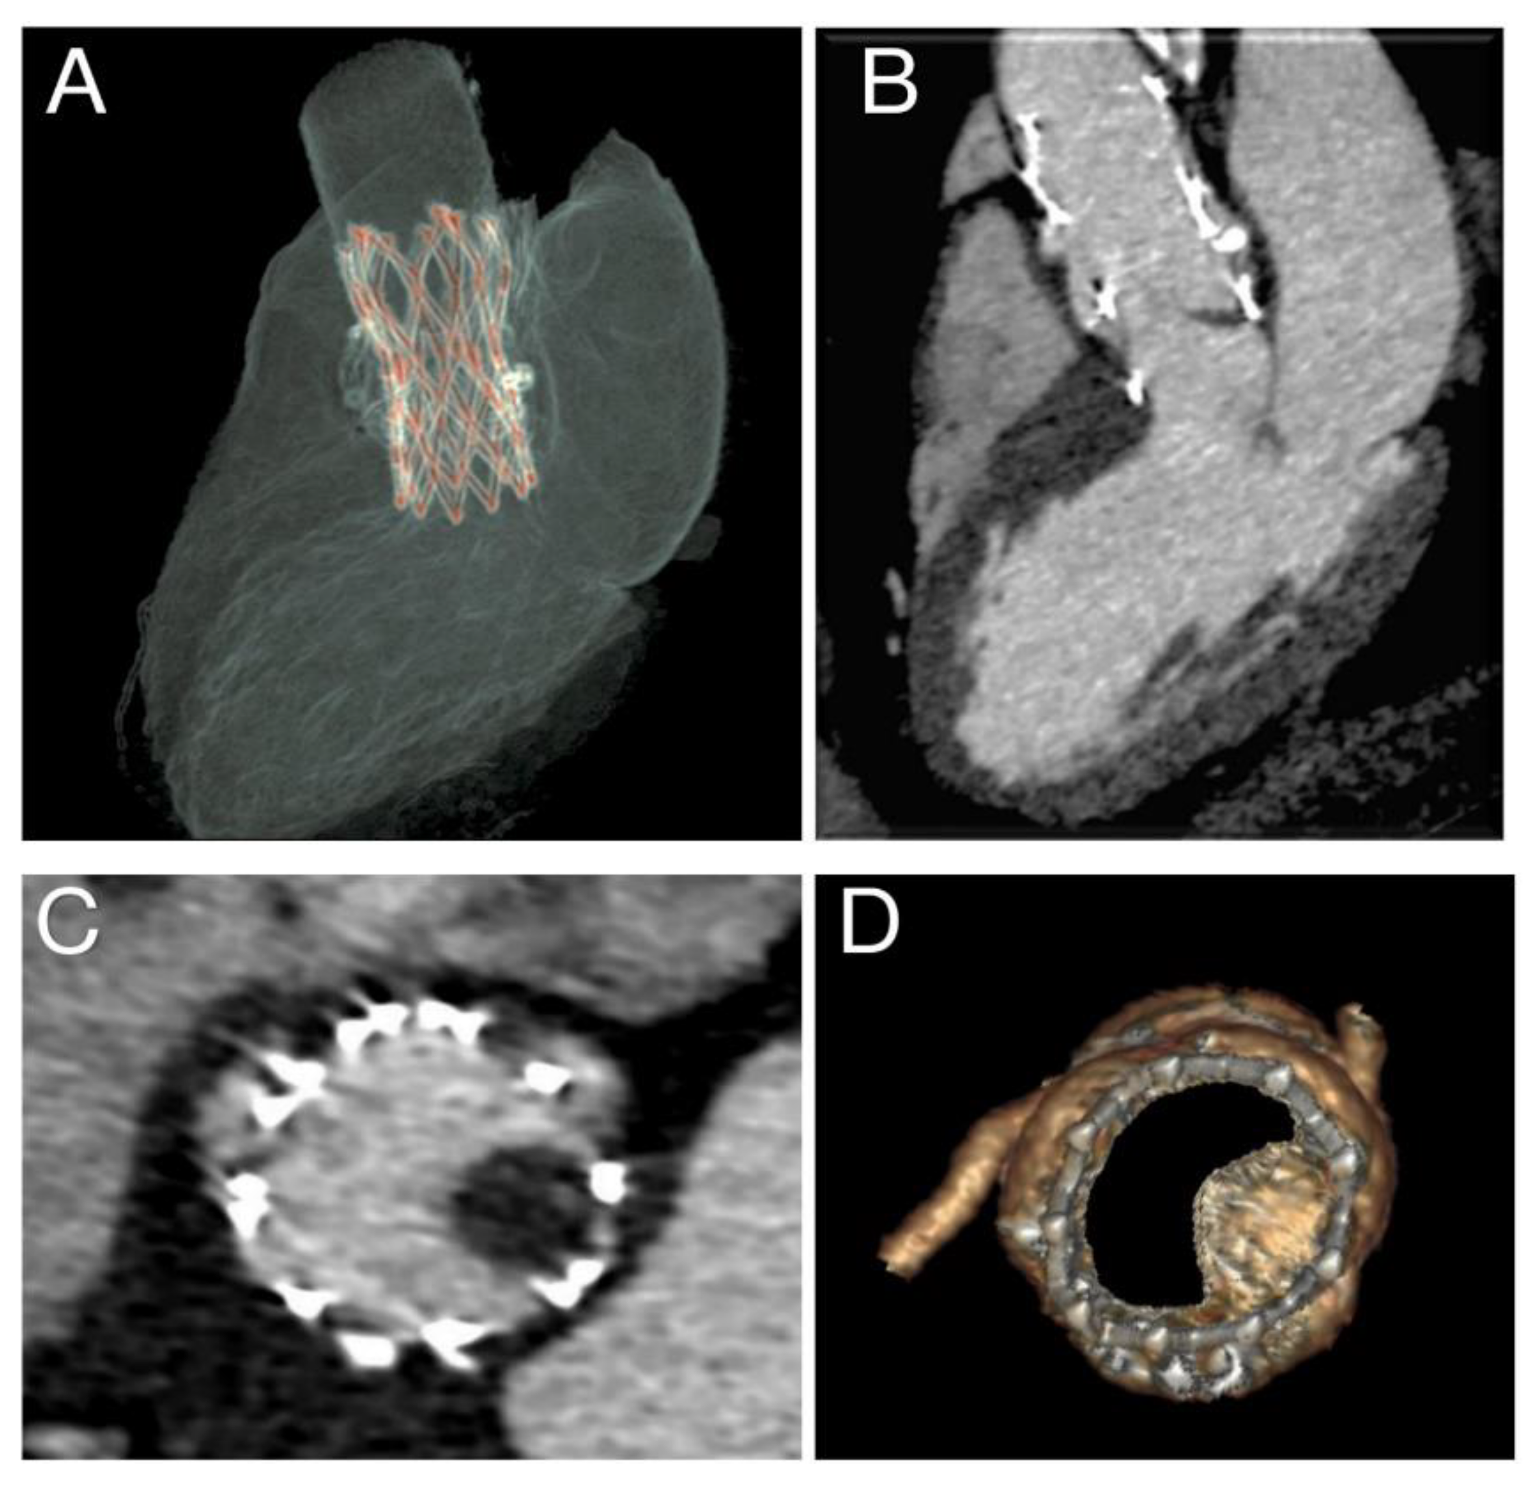

3.2. Phase 2—Simulation of the Entire Clinical Procedure after Analysis of the Acquired Data

3.3. Phase 3—Post-Processing of the Simulation Results and Comparison with Follow-Up Data